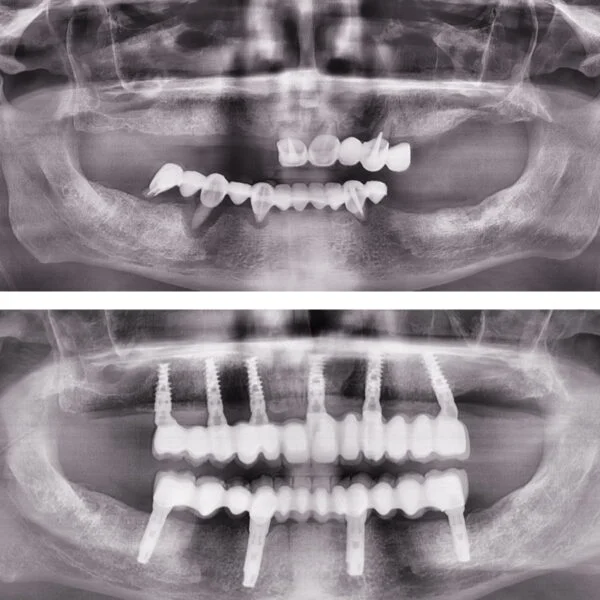

Implantul dentar este adesea recomandat deoarece prezintă foarte multe avantaje, iar, de multe ori, este unica soluție pentru protezarea unei edentații.